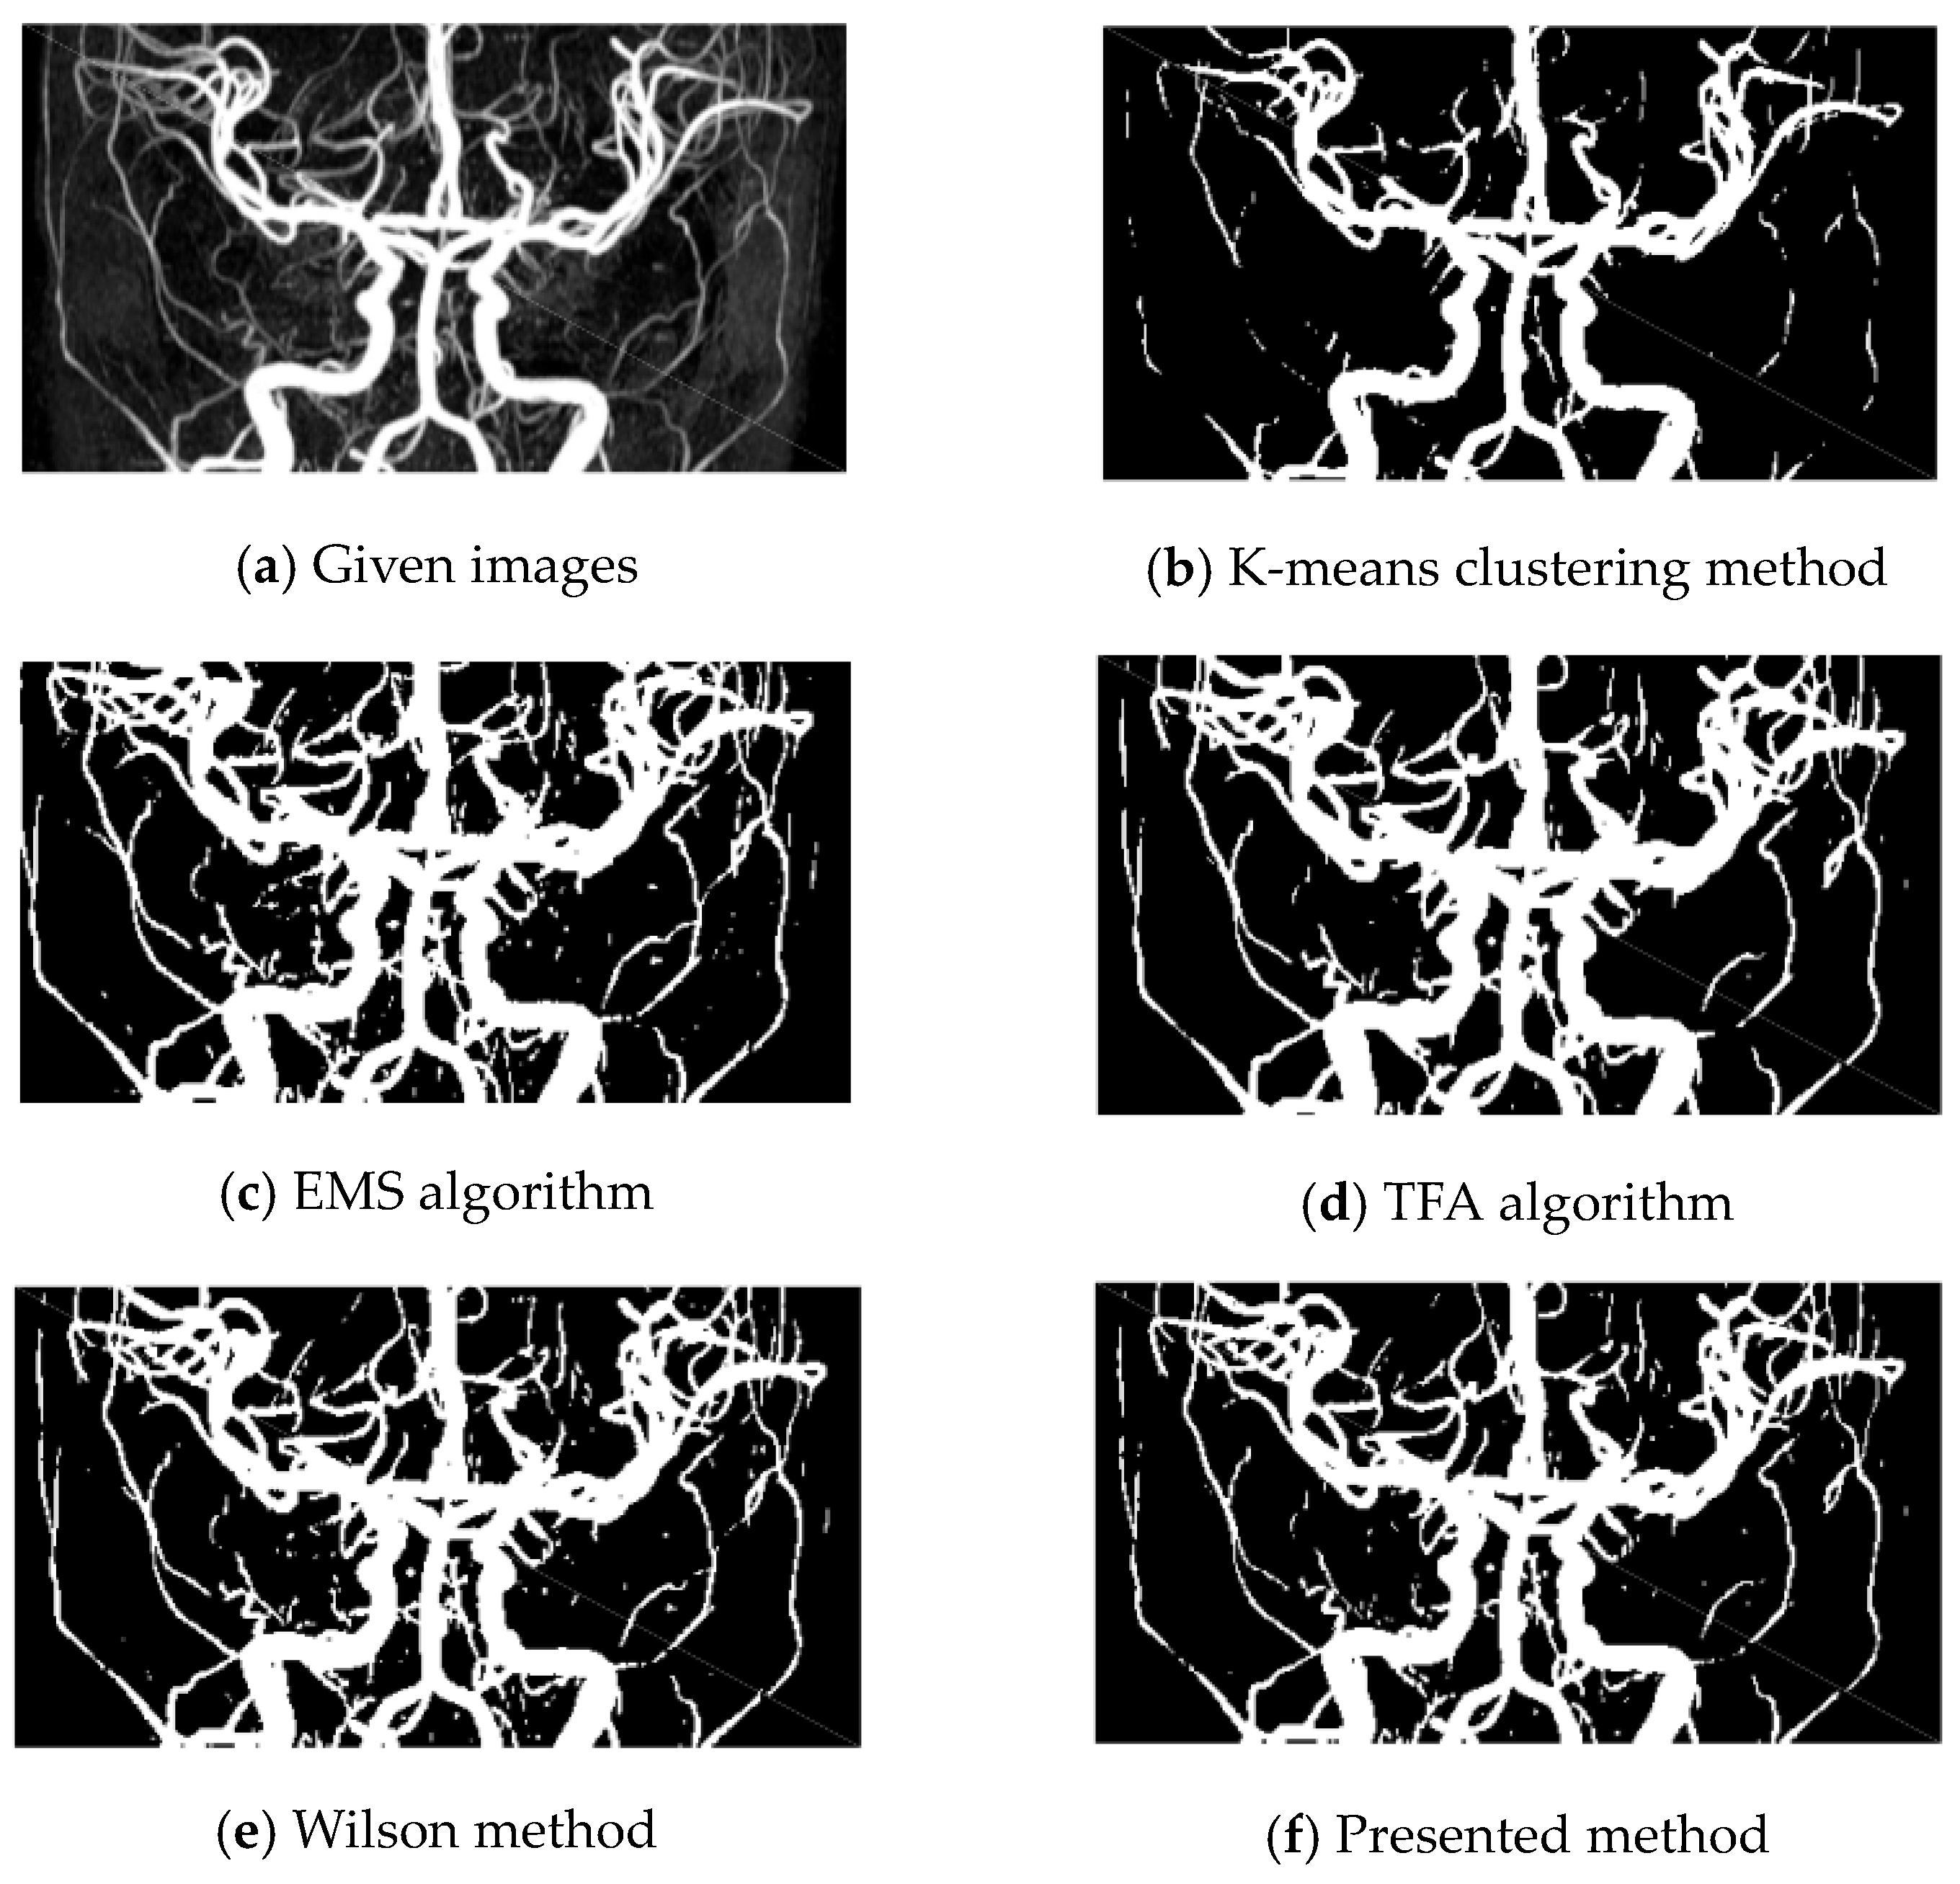

In this section, we test the presented method on three different TOF-MRA Circle of Willis Inverted MIP images. The tests have been performed on a laptop with core i7, 2 GHz processor, and 4 GB RAM. We compare our results with the K-means clustering method [46], expectation maximization segmentation [47] (EMS), the dual-tree complex wavelet tight frame algorithm [18] (TFA), and the Wilson method [19]; also, we take ϵ = 10 6 .

Based on this example, several algorithms were applied to extract vessels from a 512 × 512 TOF-MRA Circle of Willis image of the carotid vascular system. The results were compared and analyzed.

The K-means clustering method (Figure 2b) did not perform well in vessel detection, as it failed to detect most of the vessels.

The TFA algorithm (Figure 2d) also had some limitations as it failed to extract certain vessels from the image.

On the other hand, the EMS algorithm (Figure 2c), Wilson method (Figure 2e), and the presented method (Figure 2f) showed comparable results.

However, the presented method had an advantage over the other algorithms as it managed to avoid some artifacts, improving the quality of the extracted vessels.

In summary, the K-means clustering method and TFA algorithm had unsatisfactory results in vessel extraction, while the EMS algorithm, Wilson method, and the presented method showed better performance overall, with the presented method demonstrating the ability to avoid artifacts. We see that fine vessels could be detected when the presented method is employed. Our method approach is indeed helpful in finding the edges of the vascular system with low contrast.

Figure 2. Circle of Willis coronal. (a) Given image; (be), results by K-means, EMS, TFA, and Wilson methods, respectively; (f) results by the presented method for Example 1.